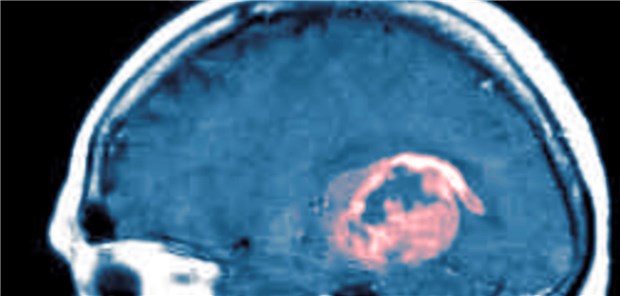

MRT-Aufnahme eines Patienten mit Glioblastom. Patienten mit Stadium IV haben noch immer eine schlechte Prognose.

© Arteria Photography

Erste Erfolge bei Gliom mit apathogenem Viruskonstrukt